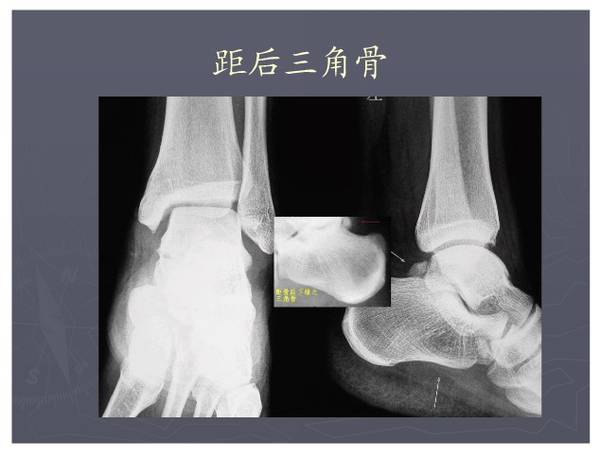

常见异常副骨或籽骨

在足部发生率最高,如副舟骨、距上骨、胫下骨腓小骨等